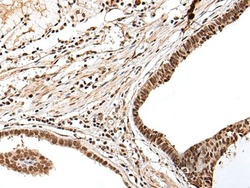

- Submitted by

- Invitrogen Antibodies (provider)

- Main image

- Experimental details

- Immunohistochemical analysis of PTOV1 in paraffin-embedded Human gastric cancer tissue using (left) PTOV1 Polyclonal Antibody (Product # PA5-67569) at a 1:25 dilution and (right) is treated with synthetic peptide. (Original magnification: x200).